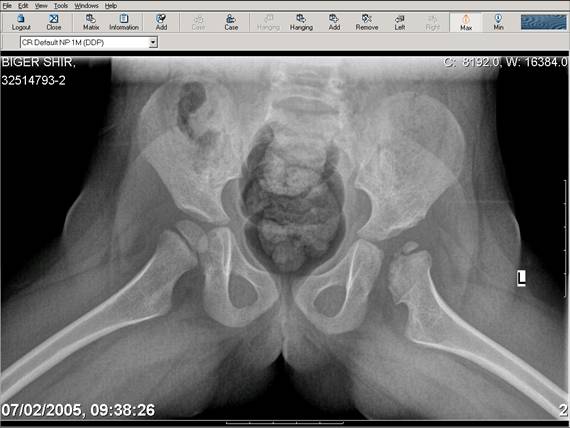

[Ortho] Врожденный вывих бедра

Navernoe Dega

Chto by ne byt goloslovnym posilau vam svoi sluchai gde sdelal vse chto napisal vyshe

Mark Eidelman